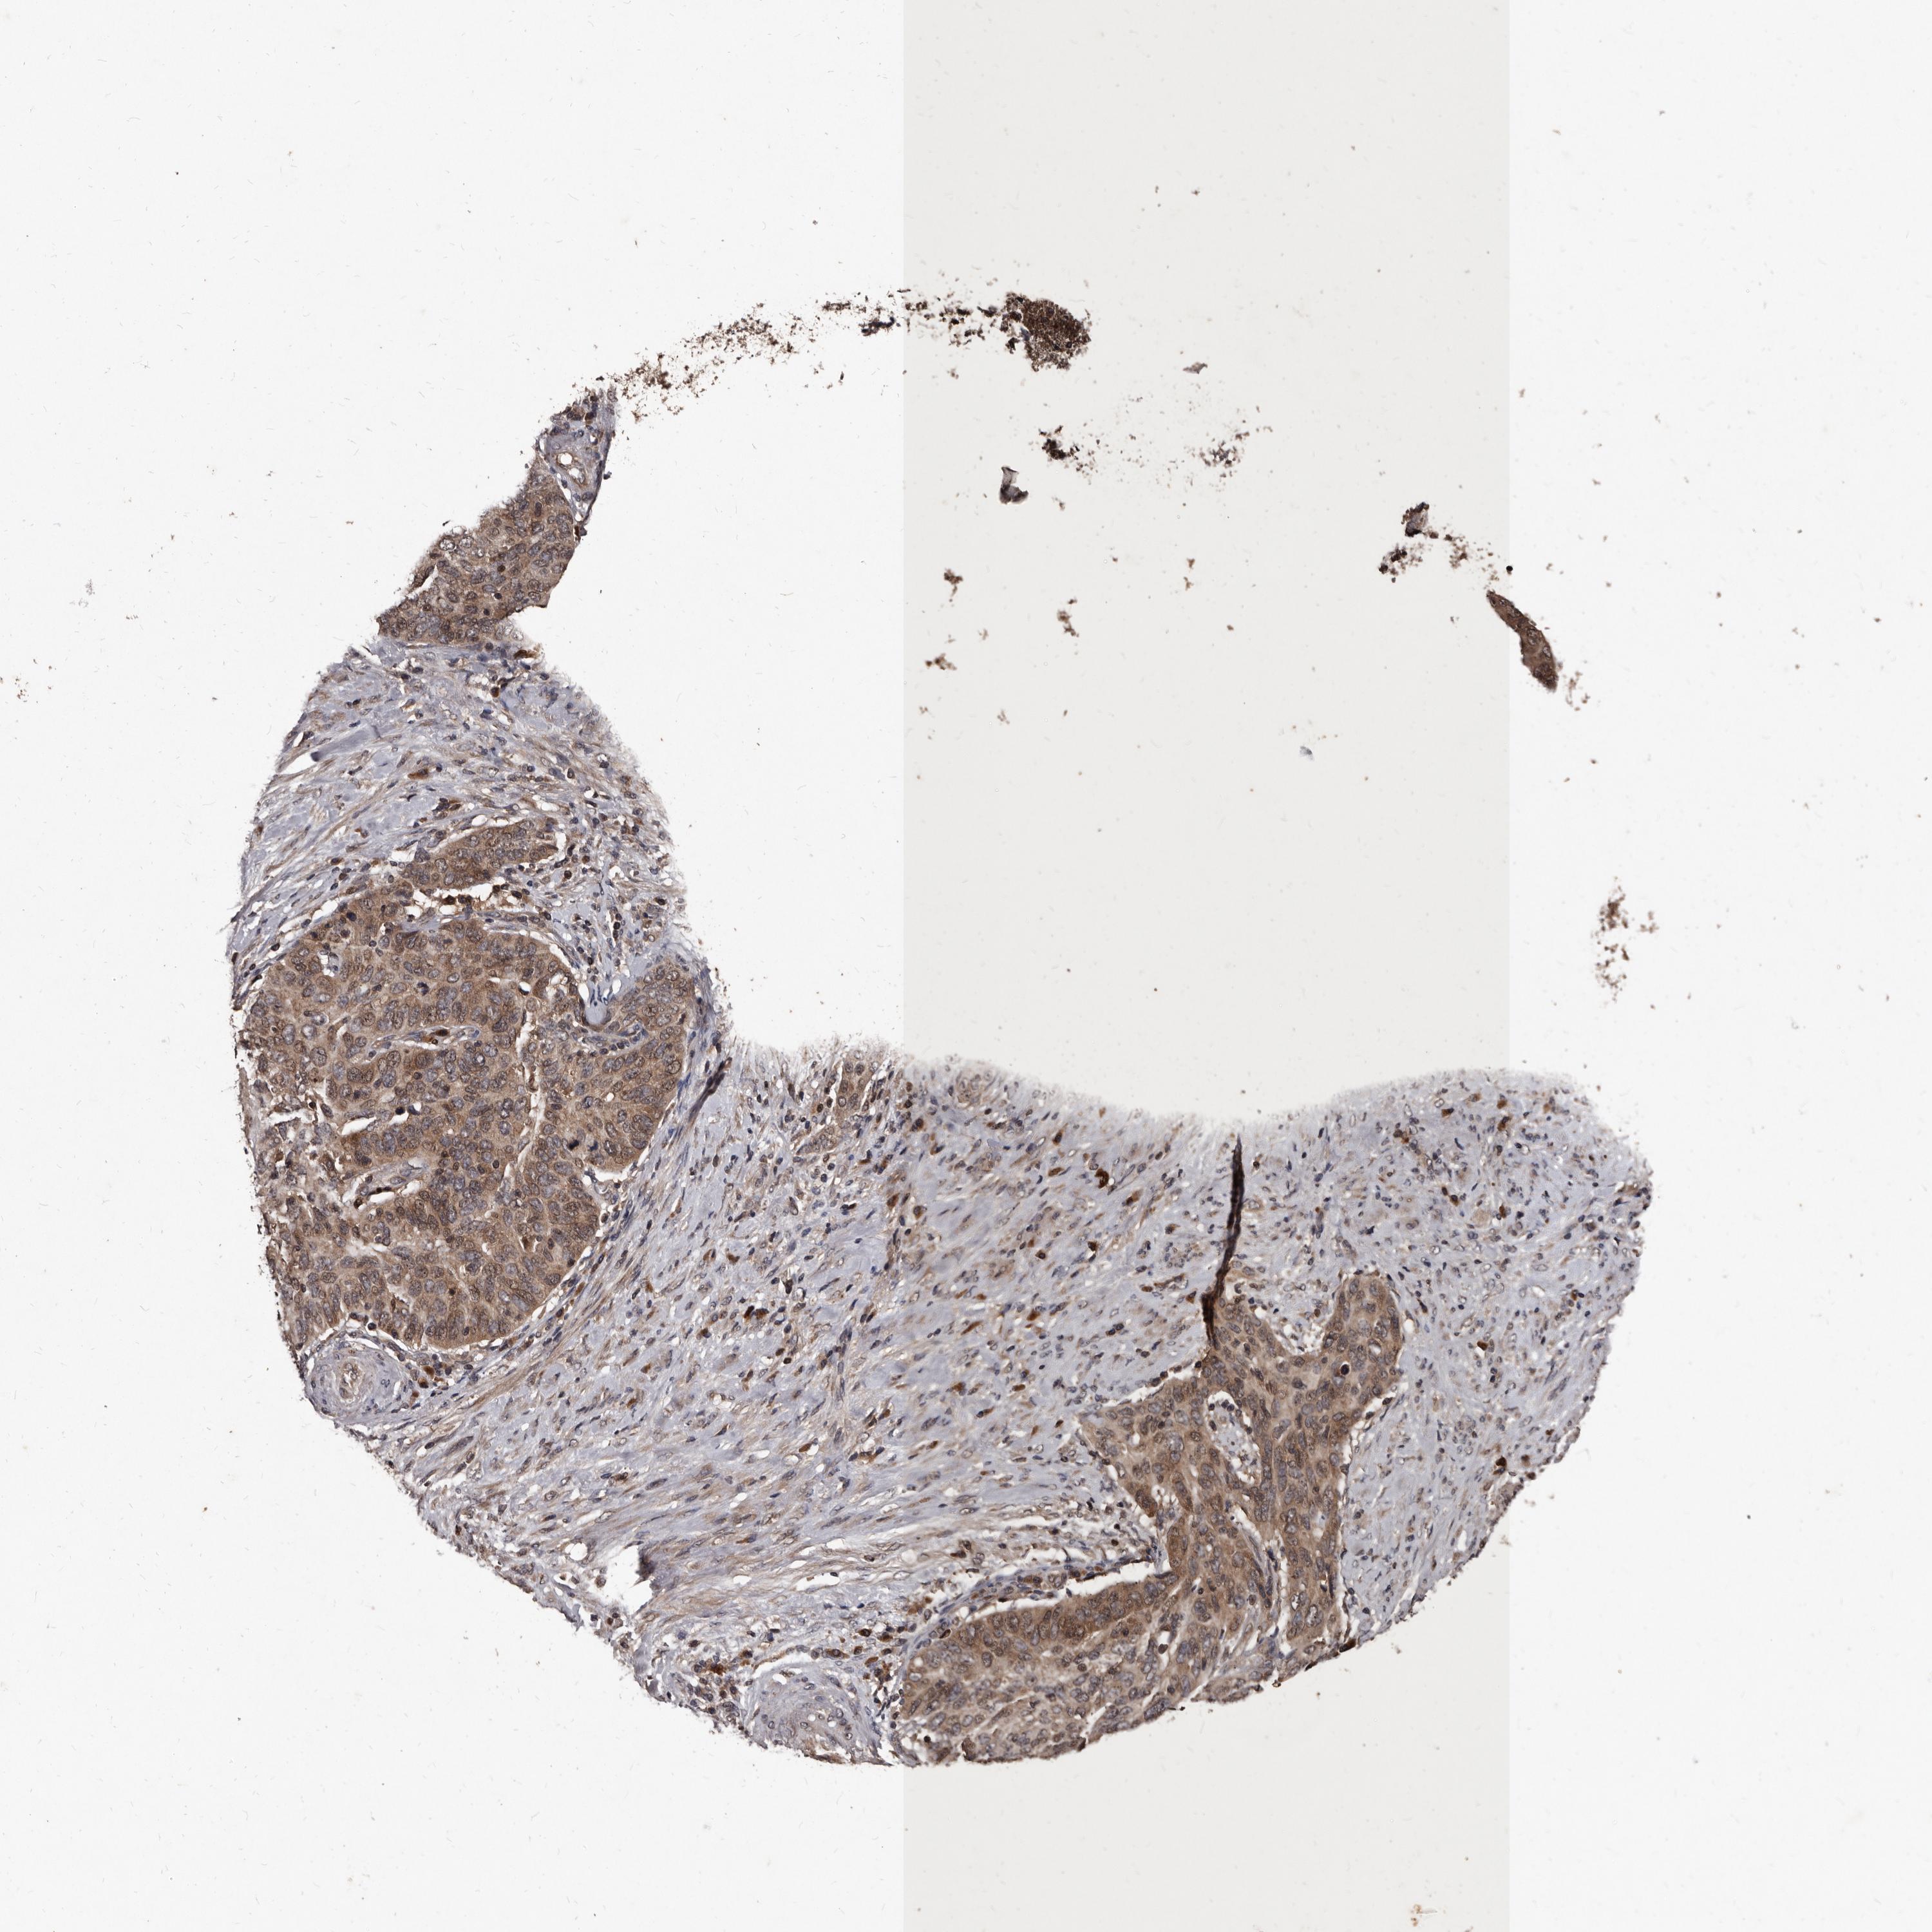

CERVICAL CANCER - Protein expressioni

A mouse-over function shows sample information and annotation data. Click on an image to view it in a full screen mode. Samples can be filtered based on level of antibody staining by selecting one or several of the following categories: high, medium, low and not detected. The assay and annotation is described here.

Note that samples used for immunohistochemistry by the Human Protein Atlas do not correspond to samples in the TCGA dataset.

Antibody stainingi

Antibody staining in the annotated cell types in the current human tissue is reported as not detected, low, medium, or high, based on conventional immunohistochemistry profiling in selected tissues. This score is based on the combination of the staining intensity and fraction of stained cells.

Each image is clickable and will lead to virtual microscopy that enables deeper exploration of all samples and also displays staining intensity scores, fraction scores and subcellular localization as well as patient and tissue information for each sample.

Antibody HPA029900

Staining

High

Medium

Low

Not detected

Intensity

Strong

Moderate

Weak

Negative

Quantity

>75%

75%-25%

<25%

None

Location

Nuclear

Cytoplasmic/membranous

Cytoplasmic/membranous,nuclear

Squamous cell carcinoma, NOS

Adenocarcinoma, NOS